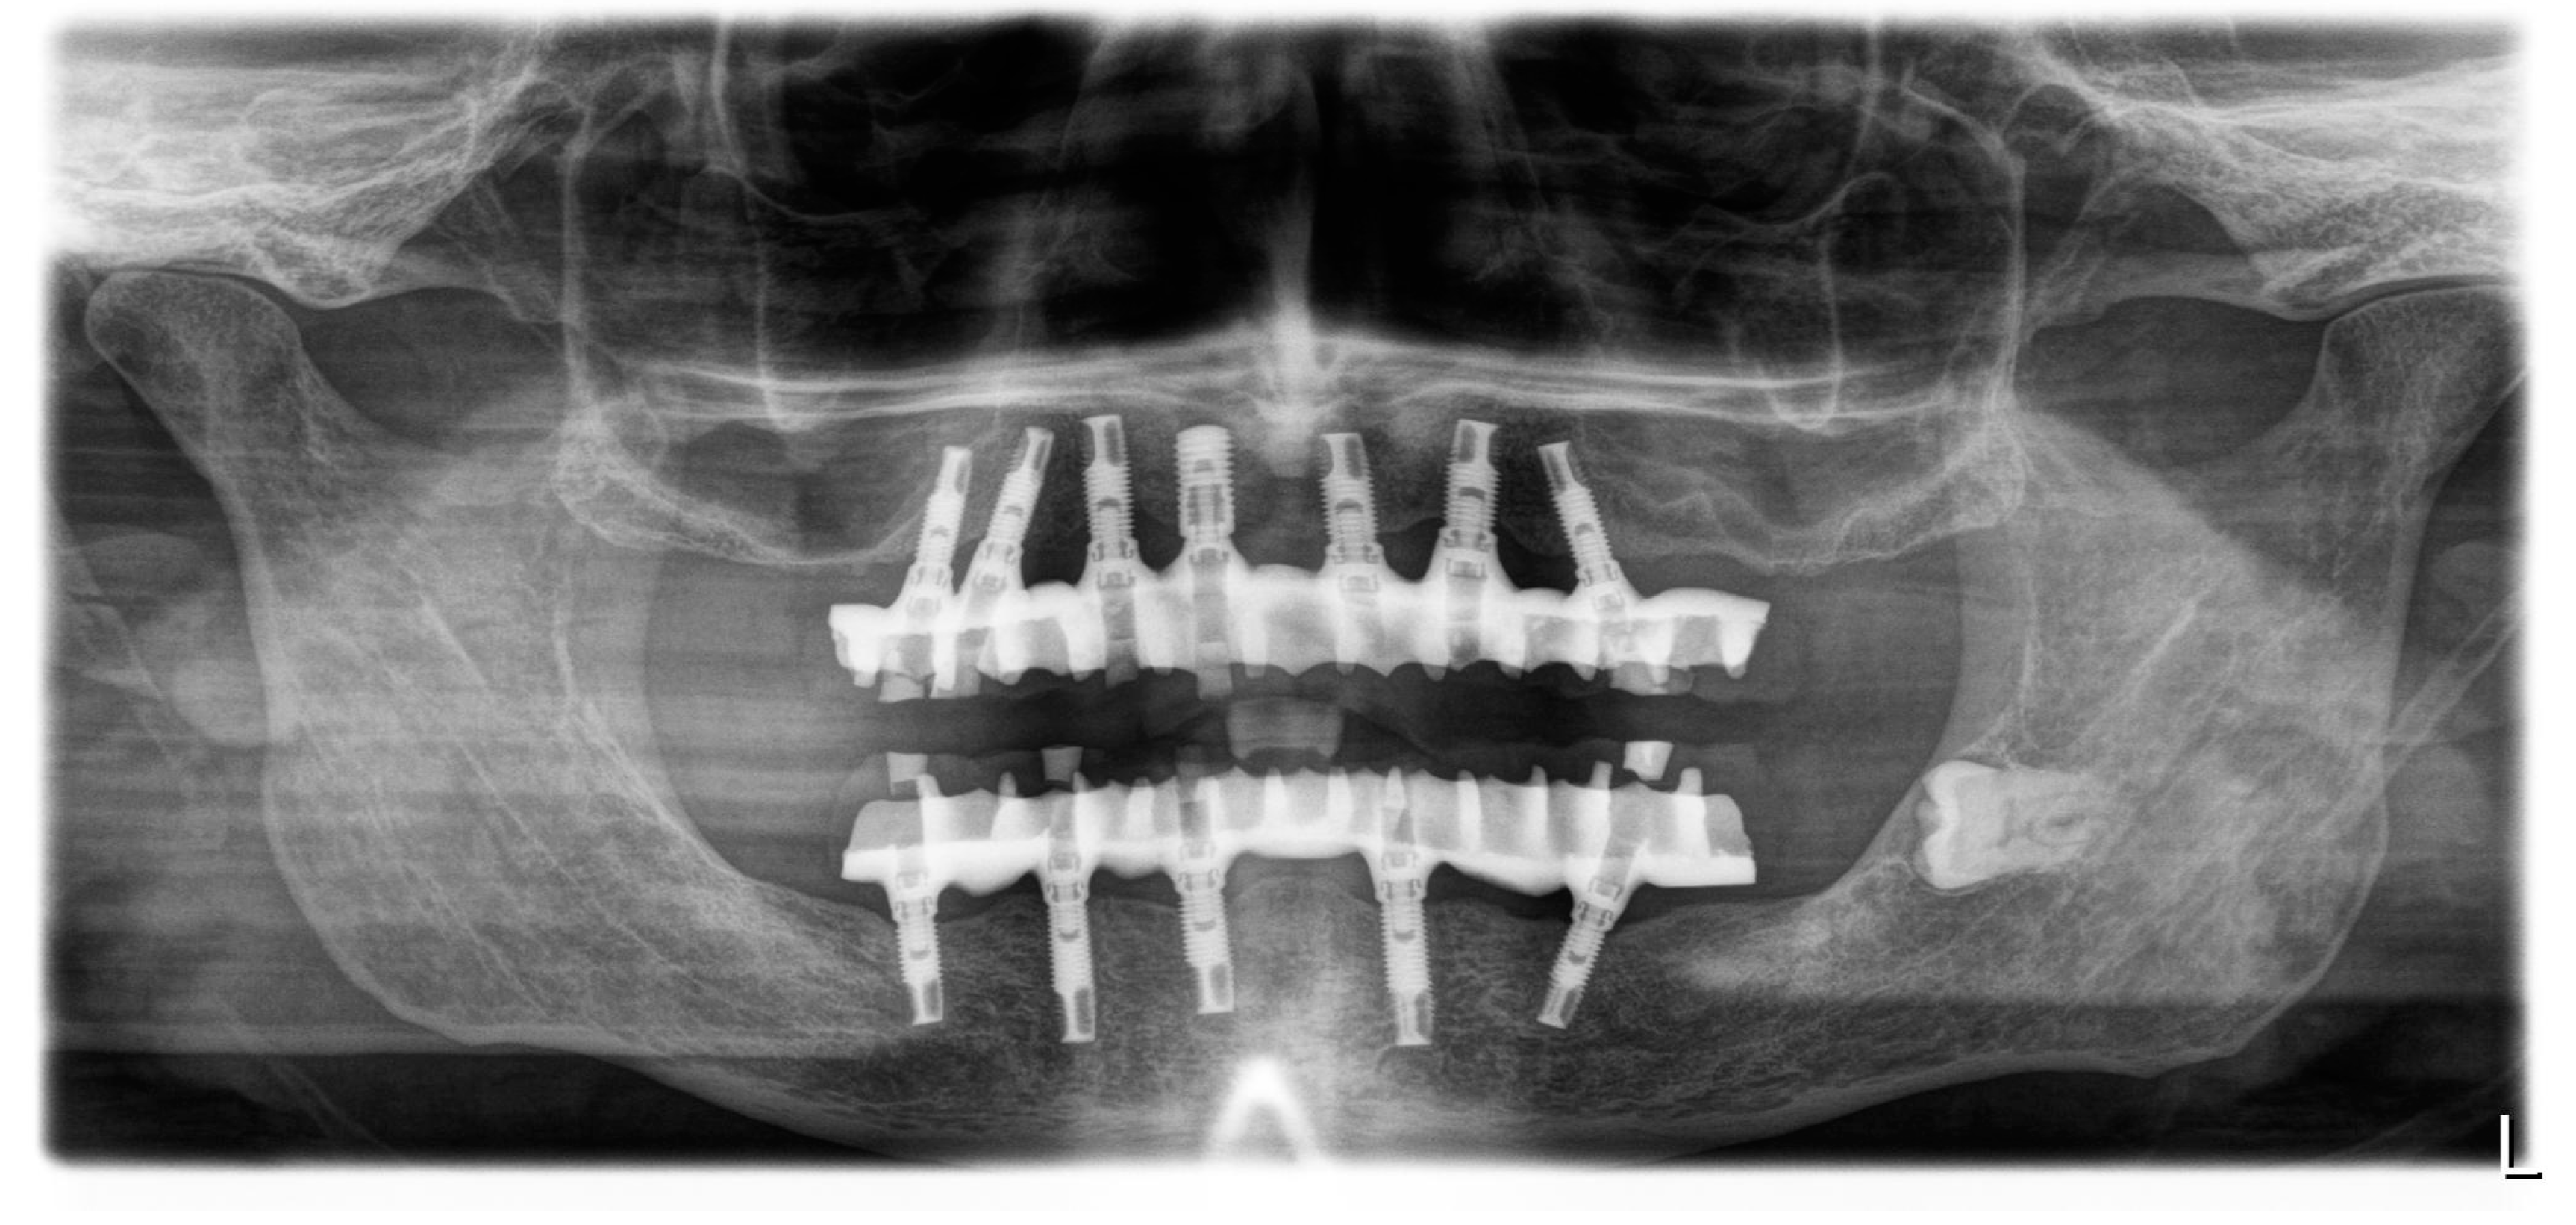

2.2. Surgical Phase